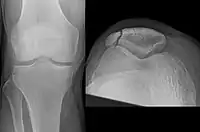

A fracture of the patella seen on a lateral view

Diagnostic methodBased on symptom, confirmed with X-rays.[3]

It typically results from a hard blow to the front of the knee or falling on the knee.[1]The patella can also be fractured indirectly. For example, a sudden contraction of the quadriceps muscle in the knee can pull apart the patella.[1]Diagnosis is based on symptoms and confirmed with X-rays.[3] In children an MRI may be required.[3]